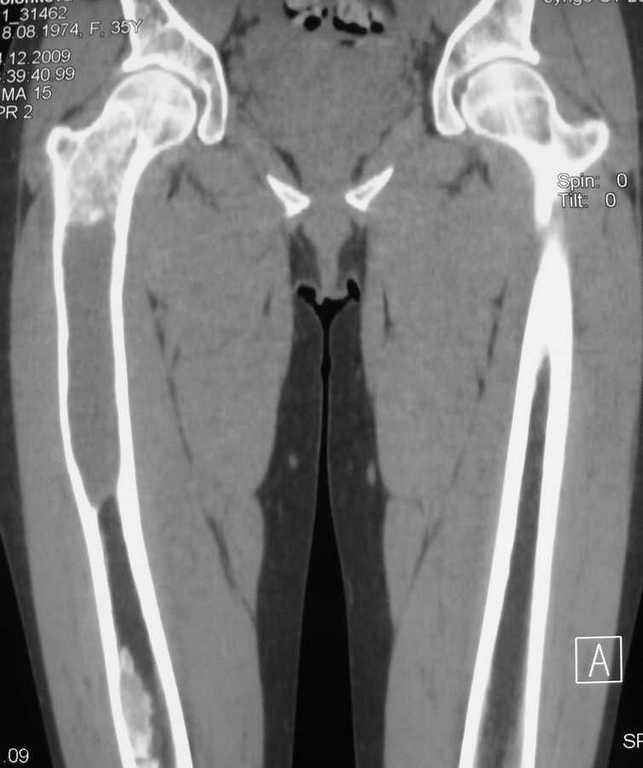

Re: Фиброзная дисплазия-продолжение

Maxim Agalakov 14 Январь 2010, 23:39

Устьянцев Ибрагимов 15 Январь 2010, 08:10

Уважаемая коллега!

Один из вариантов выбора- резекция пораженного участка, замещение дефекта по Илизарову, с последующим синостозированием или эндопротезированием.

Djoldas Kuldjanov 24 Январь 2010, 23:40

Елена,

При наличии в института сосудистых хирургов, как альтернативный метод можно было бы предложить графт как показано на снимке.

Elena Reyno 28 Январь 2010, 16:55

Большое спасибо, уважаемые коллеги! Большинством мнений склоняемся к резекции патологического очага с замещением дефекта аллокостью. Но вопрос пока остаётся открытым.

Отправитель: valeevmm 06 Февраль 2010, 10:16

Здраствуйте, коллега! Загляните, пожалуйста, на мой сайт valeevmm.ru. Там в разделе "Клинические случаи" имеется случай лечения паицента с фиброзной дисплазией бедренной кости васкуляризированным аутотрансплантатаом из фрагмента малоберцовой кости. Спасибо. С уважением, профессор Валеев (г. Уфа).

Илья Иофин 31 Январь 2010, 03:39

Я бы сделал открытый латеральный доступ к прохимальной части бедра и провёл кюретаж. Потом бы поставил штырь типа Gamma nail. Оставшуюся от кюретажа полость следует заполнить костным цементом. Проблема при фиброзной дисплазии в том, что она через год два возвращается и "съедает" аллокость, как будто операции и не делали.

Эту операцию я бы делал только если у пациента есть симптомы боли. Если их нет, то делал бы периодический рентген бедра.